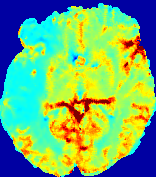

4.3.1 Advection Imaging via Advection-Diffusion

Slice #1Slice #2Slice #3Slice #4Slice #5Slice #6𝐕gt𝟐subscriptnormsuperscript𝐕gt2\|\bf{V}^{\text{gt}}\|_{2}Refer to captionRefer to captionRefer to captionRefer to captionRefer to captionRefer to caption𝐕est𝟐subscriptnormsuperscript𝐕est2\|\bf{V}^{\text{est}}\|_{2}Refer to captionRefer to captionRefer to captionRefer to captionRefer to captionRefer to captionRefer to caption1.51.51.51.21.21.20.90.90.90.60.60.60.30.30.30.00.00.0(mm/s)𝑚𝑚𝑠(mm/s)Destsuperscript𝐷estD^{\text{est}}Refer to captionRefer to captionRefer to captionRefer to captionRefer to captionRefer to captionRefer to caption0.0150.0150.0150.0120.0120.0120.0090.0090.0090.0060.0060.0060.0030.0030.0030.0000.0000.000(mm2/s)𝑚superscript𝑚2𝑠(mm^{2}/s)

Figure 14: PIANO identifiability testing: advection imaging via advection-diffusion. Top row shows 𝐕gt2subscriptnormsuperscript𝐕gt2\|{\bf{V}}^{\text{gt}}\|_{2} used for simulating ground truth pure advection. Rows below show the estimated 𝐕est2subscriptnormsuperscript𝐕est2\|{\bf{V}}^{\text{est}}\|_{2} and Destsuperscript𝐷estD^{\text{est}} on corresponding slices. Note that the plotted value scale for Destsuperscript𝐷estD^{\text{est}} is 0.01 of that for 𝐕gt2subscriptnormsuperscript𝐕gt2\|{\bf{V}}^{\text{gt}}\|_{2} and 𝐕est2subscriptnormsuperscript𝐕est2\|{\bf{V}}^{\text{est}}\|_{2}.

We use the same ‘Advection Imaging’ simulation of Sec. 4.2.1 as the concentration dataset for PIANO. However, instead of modeling pure advection (Eq. 15), we let PIANO estimate both velocity 𝐕estsuperscript𝐕est{\bf{V}}^{\text{est}} and diffusivity Destsuperscript𝐷estD^{\text{est}} via the advection-diffusion PDE (Eq. 2) underlying the proposed PIANO model. Fig. 14 shows the estimated 𝐕est2,subscriptnormsuperscript𝐕est2\|{\bf{V}}^{\text{est}}\|_{2}, and Destsuperscript𝐷estD^{\text{est}} fields for one patient. Although PIANO has the freedom to estimate both a velocity and a diffusivity field from pure advection, PIANO differentiates well between advection and diffusion: the estimated 𝐕est2subscriptnormsuperscript𝐕est2\|{\bf{V}}^{\text{est}}\|_{2} successfully reproduces the ground truth 𝐕gt2subscriptnormsuperscript𝐕gt2\|{\bf{V}}^{\text{gt}}\|_{2} governing the simulated advection process, just as it already did in the ‘Advection Imaging via Advection’ test (Fig. 12). More importantly, the estimated diffusivity Destsuperscript𝐷estD^{\text{est}} is orders of magnitudes smaller than 𝐕est2subscriptnormsuperscript𝐕est2\|{\bf{V}}^{\text{est}}\|_{2}, indicating the estimated diffusion is negligible compared to the estimated advection, which is highly consistent with the underlying pure advection of the simulated data.